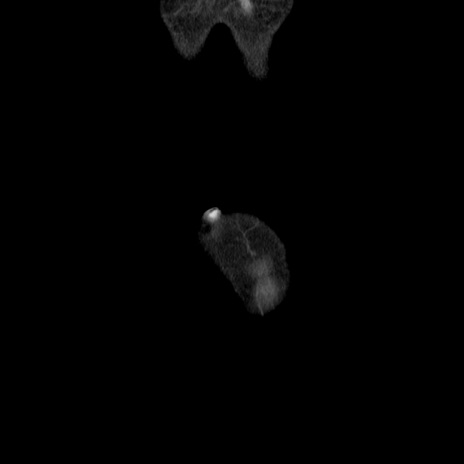

横断像